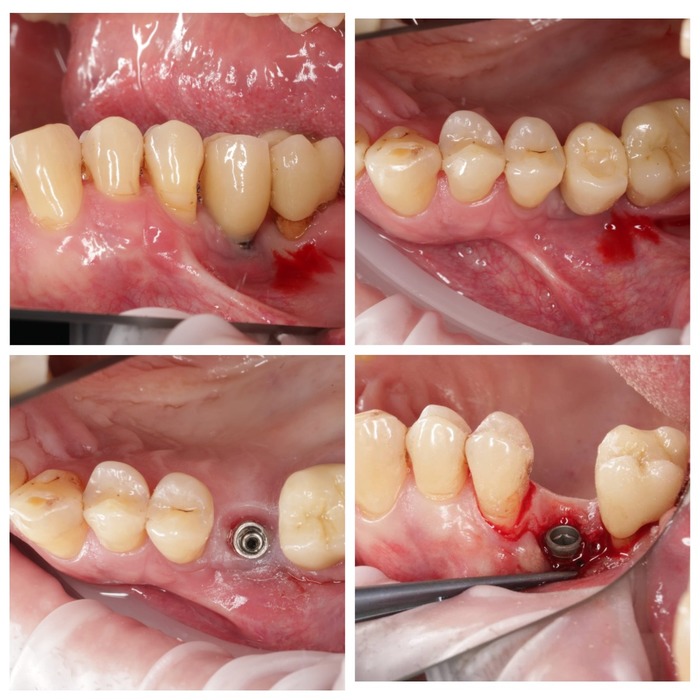

Это мой коллега Андрей переделывал за уважаемой чешской клиникой